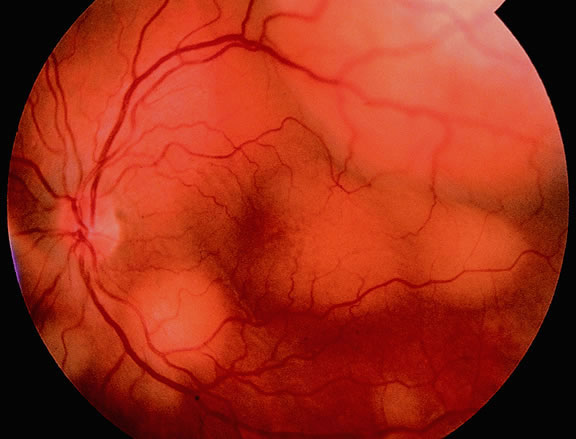

Many choroidal melanomas have a characteristic mushroom or collar button configuration that results when the tumor breaks through Bruch's membrane (Figs. 19, 20, 21, and 22). In such cases there is often secondary choroidal, subretinal, or vitreous hemorrhage. Dilated, intrinsic vessels often are evident in the mushrooming dome of nonpigmented melanomas. The vessels are obscured in more pigmented tumors.48

Fig. 19. Fundus photo of mushroom-shaped choroidal melanoma with nonpigmented dome. Configuration indicates that tumor has ruptured through Bruch's membrane.

The characteristic fluorangiographic features of uveal melanoma include mottled hyperfluorescence in the vascular filling phases and diffuse late staining of the mass and surrounding subretinal fluid. A characteristic double circulation in which both the retinal vessels and the choroidal vessels in the tumor are readily evident may be shown by larger amelanotic tumors, particularly those that have perforated Bruch's membrane. The prominent blood vessels seen in amelanotic mushroom-shaped melanomas may impart a pseudoangiomatous appearance to the lesion.48